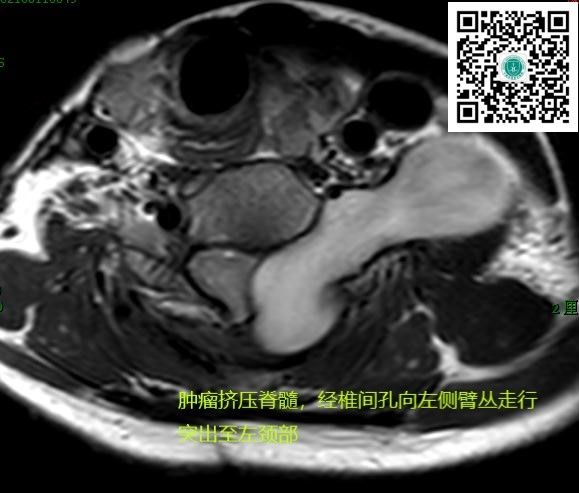

患者来院时四肢肌力4级,搀扶才能站立,其中左上肢精细运动变差。

周迎春教授考虑到患者不仅有椎管内外占位的问题,还合并脊柱畸形,而要完整切除肿瘤必须打开左侧椎间孔,将使得脊柱畸形进一步加重,于是为患者制定了前后路联合手术方案:切除肿瘤+脊柱矫形。

经后路切除椎管及椎间孔肿瘤,给肿瘤“除根”,为脊髓“减负”。

经颈前路切除残余肿瘤,臂丛神经保护完好。